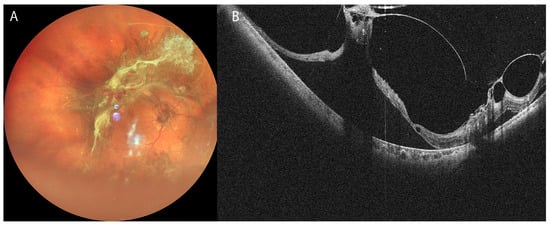

3.2. Retinal Detachment

- Takahashi, H.; Uramoto, K.; Ohno-Matsui, K. Ultra-Widefield Optical Coherence Tomography For Retinal Detachment With Proliferative Vitreoretinopathy. Retin. Cases Brief. Rep. 2022, 16, 355–359. [Google Scholar] [CrossRef] [PubMed]

- Martins Melo, I.; Bansal, A.; Naidu, S.; Oquendo, P.L.; Hamli, H.; Lee, W.W.; Muni, R.H. Morphologic Stages of Rhegmatogenous Retinal Detachment Assessed Using Swept-Source OCT. Ophthalmol. Retin. 2023, 7, 398–405. [Google Scholar] [CrossRef]

- El-Sehemy, A.; Martins Melo, I.; Pecaku, A.; Zajner, C.; Naidu, S.; Motekalem, Y.; Muni, R.H. Postoperative Photoreceptor Integrity and Anatomical Outcomes Based On Presenting Morphologic Stage Of Rhegmatogenous Retinal Detachment. Retina 2024, 44, 756–763. [Google Scholar] [CrossRef] [PubMed]

- Martins Melo, I.; Naidu, S.; Pecaku, A.; Zajner, C.; Bansal, A.; Oquendo, P.L.; Lee, W.W.; Muni, R.H. Impact of Baseline Morphologic Stage of Rhegmatogenous Retinal Detachment on Postoperative Visual Acuity. Ophthalmol. Retin. 2024, 8, 624–632. [Google Scholar] [CrossRef]

- Lee, W.W.; Francisconi, C.L.M.; Marafon, S.B.; Juncal, V.R.; Chaudhary, V.; Hillier, R.J.; Muni, R.H. Imaging Predictors Of Functional Outcomes After Rhegmatogenous Retinal Detachment Repair. Retina 2024, 44, 1758–1765. [Google Scholar] [CrossRef]